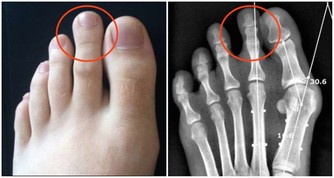

1.急性期:起病急驟,疼痛劇烈,肌肉痙攣,關節活動受限。夜間疼痛加重,難以入眠。壓痛範圍廣泛。X線檢查一般無異常發現。